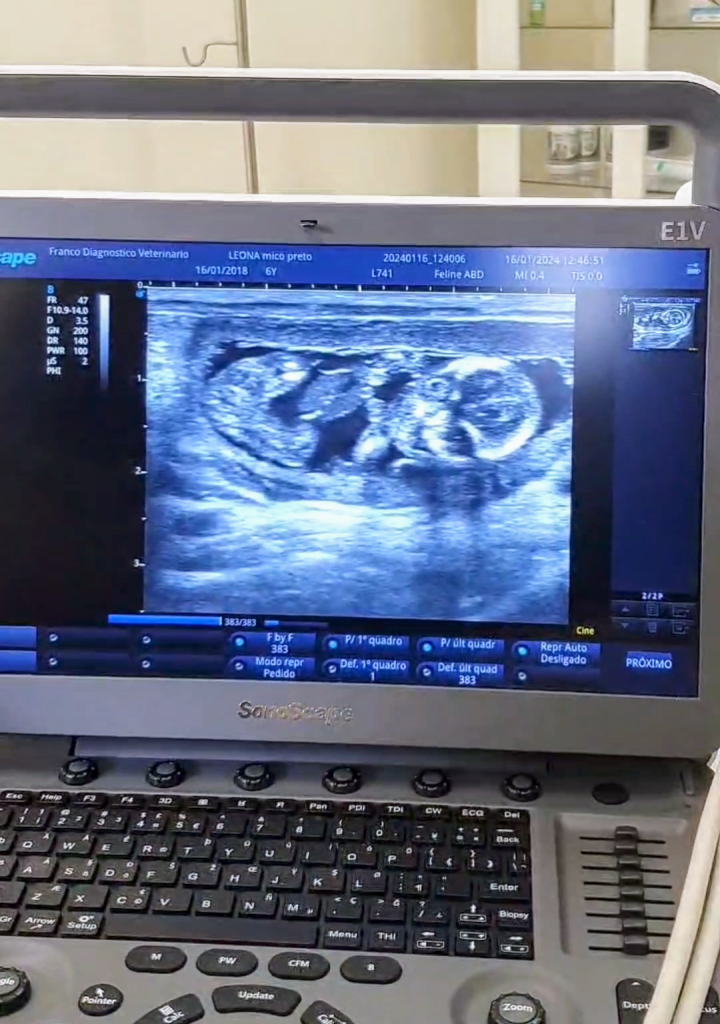

O Dia do Mico-Leão-Preto, nesta quinta-feira (29), ganha motivo duplo para comemoração. Isto porque um ultrassom em uma fêmea revelou a chegada em breve de dois novos animais da espécie ameaçada de extinção no Núcleo de Pesquisa e Conservação de Fauna Silvestre do Estado de São Paulo (CECFAU), vinculado à Secretaria de Meio Ambiente, Infraestrutura e Logística (SEMIL). O mico-leão-preto é considerado patrimônio ambiental e símbolo do estado de São Paulo.